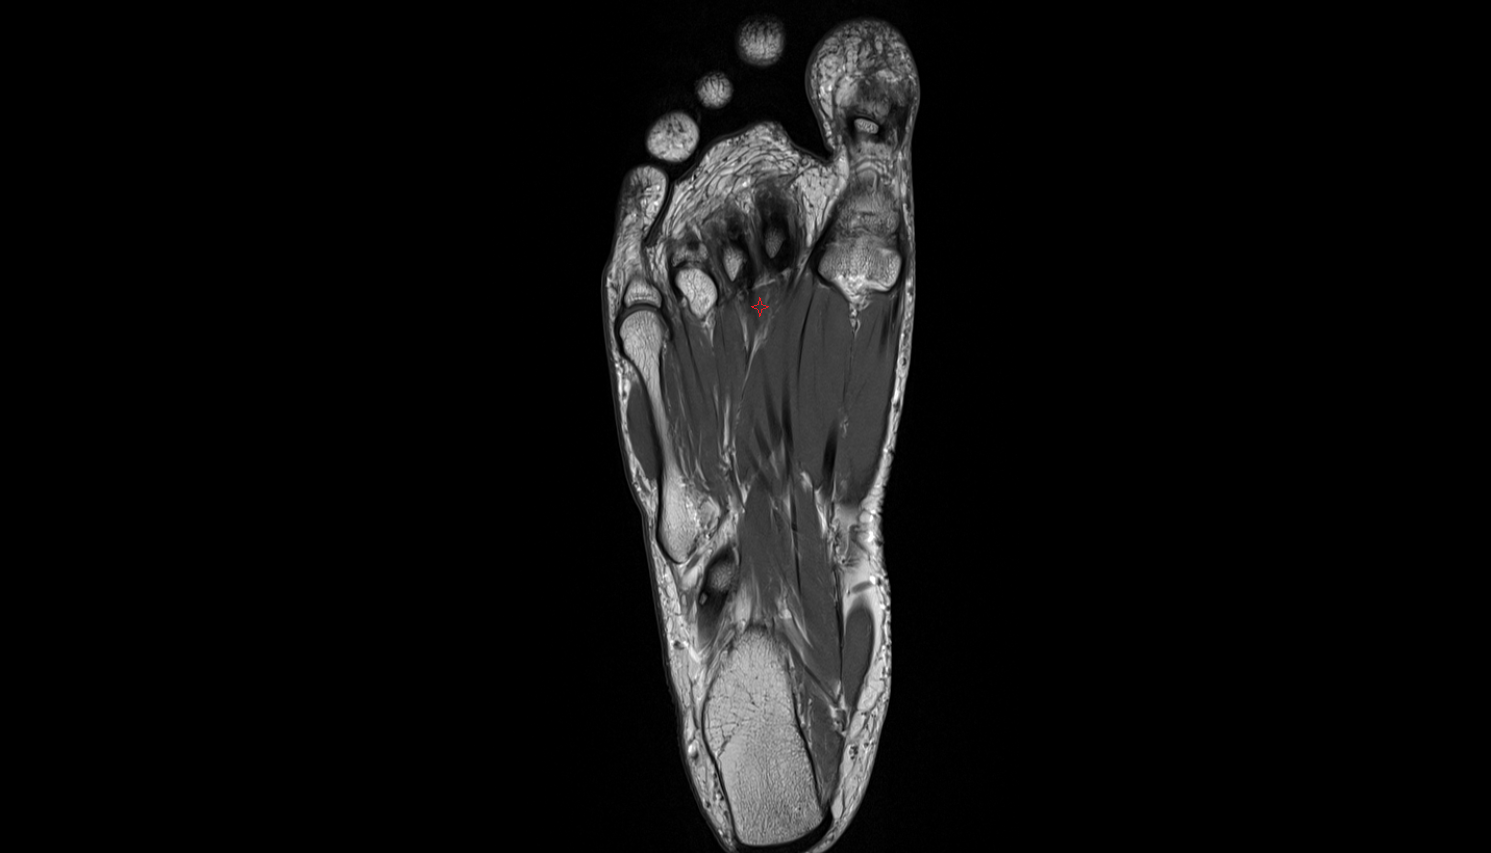

- Plantar aponeurosis